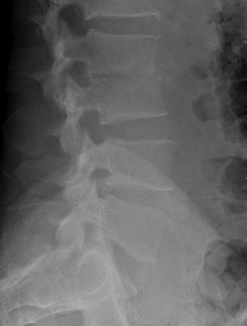

Xray / MRI

Osteomyelitis changes include

- confluent hypointensity of involved bodies on T1

- hyperintensity of involved bone and disc on T2

- loss of distinction of involved bone & disc

- abnormal disc appearance